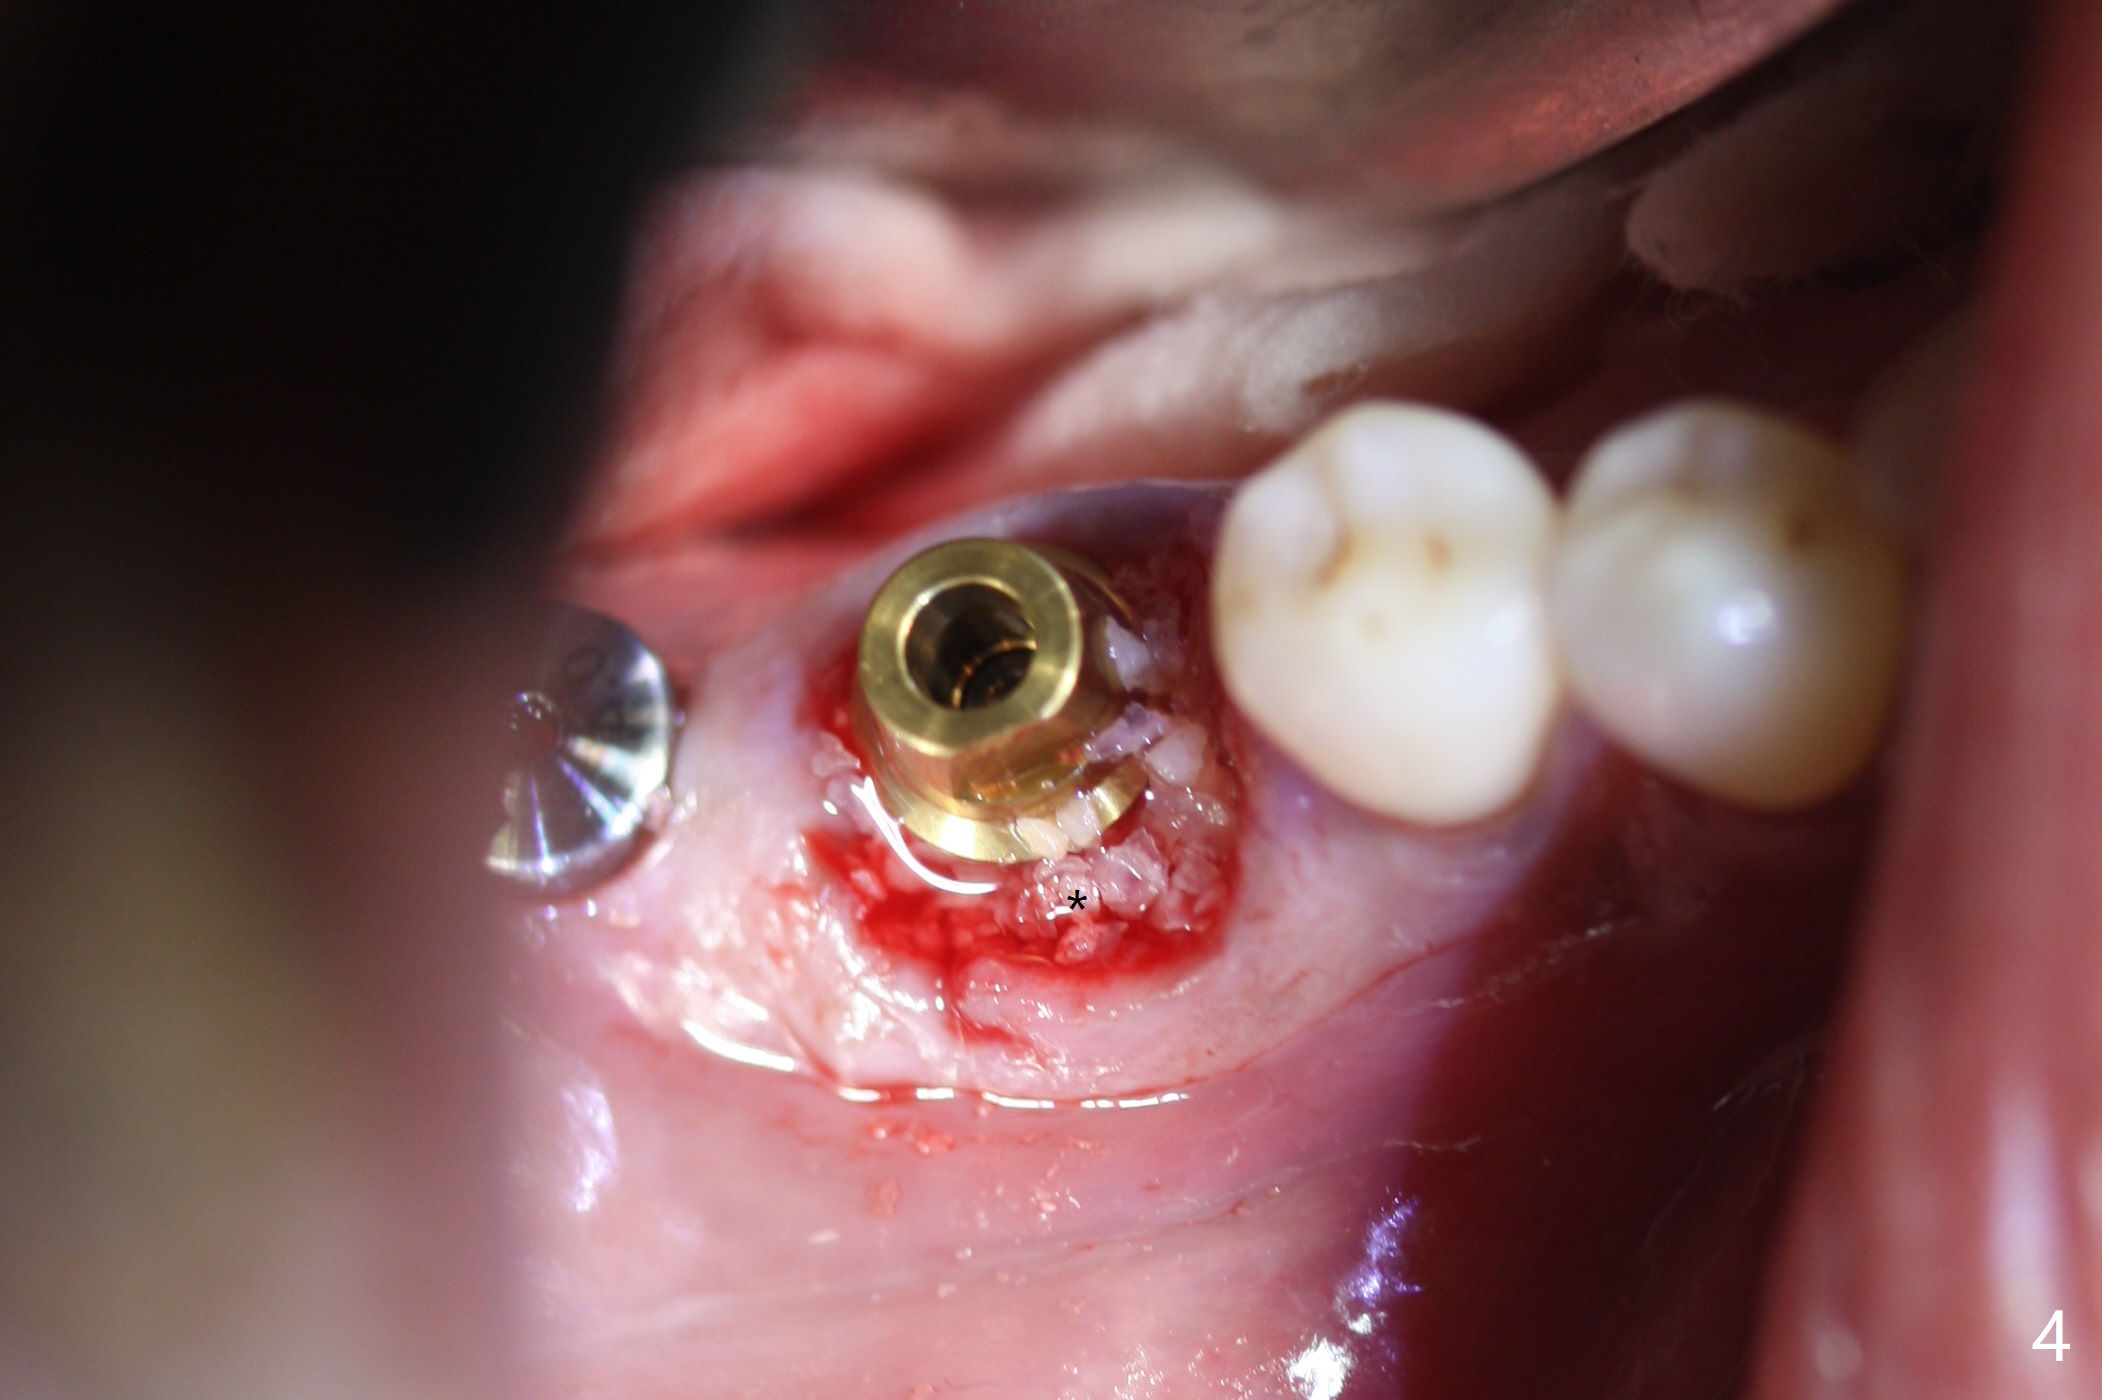

Abutment vs. Definitive One

After extraction of the tooth #30 with lingual subgingival fracture (Fig.1), the septum is fairly large (Fig.2 S). A bony vertical anchor pin (Fig.3 *) is inserted in the septum following pointed drill to to stabilize the guide during osteotomy and implant placement of #31. When the latter is finished, a fixture anchor pin is used at #31 as planned. A healing abutment is placed at #31 because of supraeruption of the tooth #2 (Fig.4,5), while a cementation abutment is placed at #30 (Fig.5) with autogenous bone (from drills) and allograft placed around it (*, Fig.6). Finally an immediate nonfunctional provisional is fabricated to keep the bone graft in place (Fig.7 P). The bone graft remains in place gel-like nearly 1 month postop (Fig.8). CBCT axial section shows that there is not enough space for mini implant placement at the tooth #2 (Fig.9). Restoration-induced intrusion will be conducted using the implants at #30 and 31 three-4 months postop. The buccal gingiva (Fig.10 *) is lingual to the provisional (P) nearly 1.5 months postop. When the provisional is removed, it appears that the mesiobuccal bone graft has lost (Fig.11). Two days later, the cementation abutment is loose and removed; the gingival cuff looks healthy (Fig.12). A 6.8x5 mm healing abutment is placed (Fig.13). In 2.5 to 3 months, abutments will be placed at #30 and 31. Splinted provisional will be fabricated over supraocclusion to intrude the tooth #2 with a stop on the left side. Surprisingly the patient agrees to intrude the tooth #2 with 2 mini implants 5.5 months postop (Fig.14,15). However, the miniimplants dislodged. Due to coronavirus, the implants are restored with heavy abutment and opposing tooth trimming 1 year 9 months postop (Fig.16). Magicore should have been placed instead.